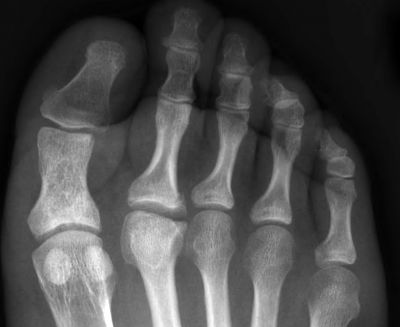

На 24 ноември от 9.00ч. до 17.00ч. в сградата на РЗИ - Варна ще се проведе поредната профилактична скринингова и информационна кампания за определяне на личния риск от остеопороза и измерване на костната плътност с преносим ултразвуков апарат. На място ще се извършват консултации по профилактика на остеопорозата чрез подходящ хранителен и двигателен режим.